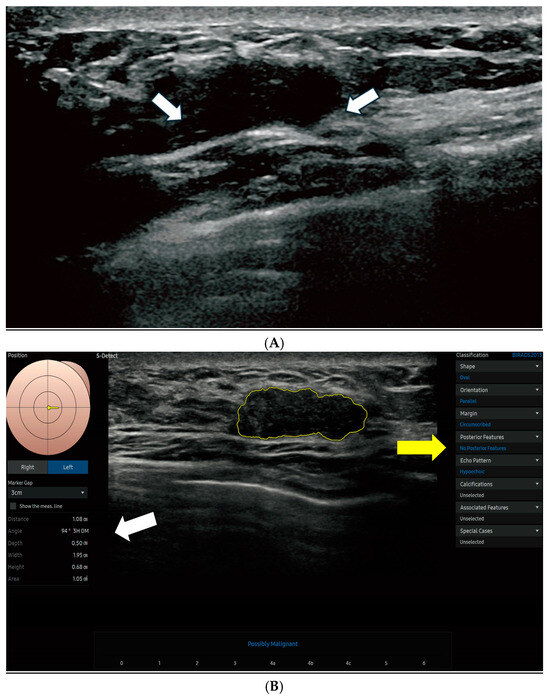

The S-Detect AI system accurately outlined lesion boundaries and calculated the ROI area, which helps standardize analytical measurements across cases. Morphological characteristics were evaluated based on the 5th edition of the ACR BI-RADS lexicon, including shape (oval, round, lobular, or irregular), orientation (parallel or non-parallel), margin (circumscribed, indistinct, angular, microlobulated, or spiculated), posterior acoustic features (none, enhancement, shadowing, or combined), and internal echo patterns (anechoic, hyperechoic, isoechoic, hypoechoic, or complex). Figure 2 displays the S-Detect AI system’s processed ultrasound images of lesions.

Figure 2. Breast ultrasound and S-Detect AI analysis in a 44-year-old woman with a BI-RADS 4A lesion. (A) B-mode ultrasound image of the left breast demonstrates a hypoechoic lesion (arrows), initially categorized as BI-RADS 4A by the interpreting radiologist. (B) The S-Detect AI delineates the lesion margins and provides associated quantitative size parameters (white arrow): distance, 1.08 cm; angle, 94°; depth, 0.50 cm; width, 1.95 cm; height, 0.68 cm; and area, 1.05 cm2. The AI-generated BI-RADS lexicon assessment (yellow arrow) characterizes the lesion as oval, parallel-oriented, circumscribed, hypoechoic, and without posterior acoustic features.